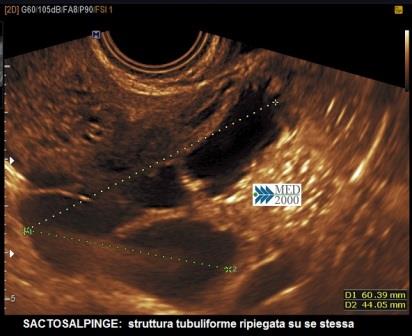

Superata la fase acuta dell'infiammazione annessiale possono esitare, anche a distanza di molto tempo, alterazioni dell'ecoarchitettura degli annessi che configurano il quadro della idrosalpinge o sactosalpinge. Le caratteristiche ecografiche della idrosalpinge, diverse dai quadri delle forme acute, sono le seguenti:

le pareti tubariche, a differenza che nelle forme acute, sono sottili, di diametro < 5 mm.; la salpinge appare dilatata per l'accumulo di liquido e assume una conformazione contorta, ripiegata su se stessa tanto da creare immagini di setti incompleti che, a differenza delle forme acute, sono sottili e di diametro < 5 mm.